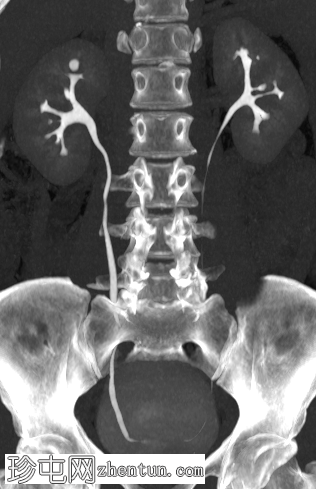

双侧肾盏憩室

冠状位

最大强度投影(MIP)

膀胱部分充盈,未见可疑局灶性肿块。上尿路未见可疑尿路上皮异常。右肾上极肾盏可见一9毫米憩室。左肾上极肾盏可见一微小憩室。

右侧肾上腺内侧肢可见一大小为 2.2 cm 的边界清晰的脂肪密度结节,平均密度为 -90 HU,周围有纤维性假包膜包绕,很可能是脂肪瘤。

病例讨论

双肾均可见小肾盏憩室,可能为偶然发现;除此之外,上尿路未见其他可疑的尿路上皮异常,无法解释患者的症状。右侧肾上腺可见一小块边界清晰的脂肪密度病变,周围有纤维性假包膜包绕,很可能是肾上腺脂肪瘤,也可能是偶然发现。